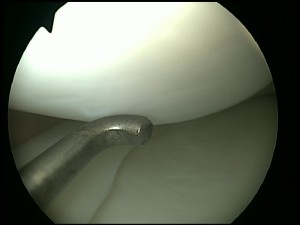

Through these incisions a special fibre optic camera allows the inside of the knee joint to be viewed and special small instruments can be used to perform surgery inside the knee. Nearly all patients are treated as day cases and therefore are allowed home the same day.